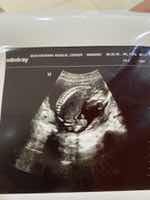

هذه صورة السونار الي تفهم فذا الموضوع تشوف هل فعلًا في التهابات ولا لا